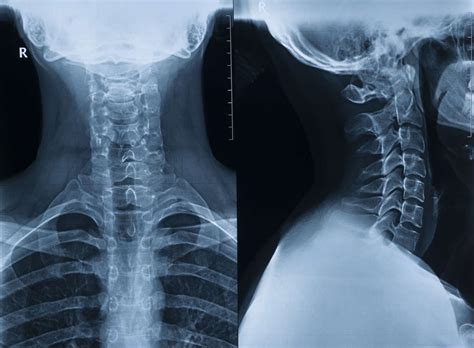

A cervical spine X-ray is a non-invasive diagnostic test that uses electromagnetic radiation to create images of the seven vertebrae located in the neck. These vertebrae, labeled C1 through C7, support the weight of the skull and facilitate head movement. When a radiologist or physician reviews these images, they are looking for specific markers of skeletal integrity.

A Normal Cervical Spine X Ray is characterized by several key features that signify a healthy alignment and bone structure:

• Proper Alignment: The vertebrae should form a smooth, gentle curve known as the lordotic curve. A "straightened" spine, often caused by muscle spasms, can indicate an underlying issue.

• Positioning: The technician will ask you to hold still in various positions—usually looking forward, sideways, and sometimes with the head tilted—to capture the spine from multiple angles.